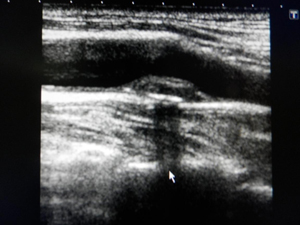

頸動脈のエコー画像。上の黒い部分が血液の通り道。

中央の盛り上がりがプラーク。

血管壁の厚みを測ります。正常値は1.0㎜以下です。1.1㎜を超えると脳梗塞の発症率が高くなるとされています。また、プラーク(コレステロールなどの塊が血管内の壁にについたもの。画像中央の盛り上がり部分)の有無を確認します。プラークは脳に飛んで血管を詰まらせる可能性があるもので、柔らかく新しいものほど血管からはがれやすいのです。超音波では、プラークの形や大きさを観察したり、プラークの硬さを推測します。